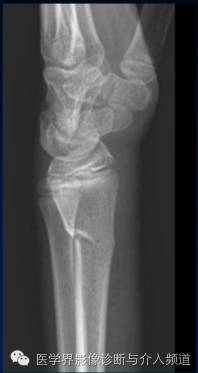

8、Barton’s骨折

桡骨远端骨折。骨折线累及桡腕关节面及桡骨远端背侧缘,为关节囊内骨折。受伤机制摔倒时候手撑地呈过伸状。

9、反Barton’s骨折

桡骨远端骨折。骨折累及桡腕关节面及桡骨掌侧缘,而Barton’s骨折累及的是桡骨背侧缘,为关节囊内骨折。受伤机制摔倒时候手撑地呈过屈状。